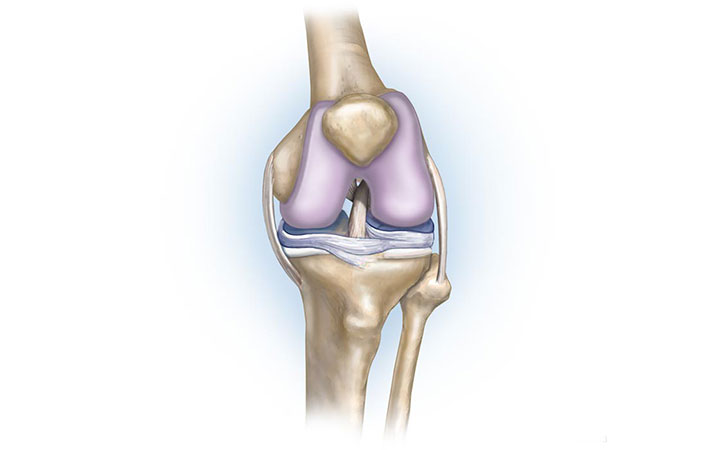

Рисунки Суставов: Анатомические Иллюстрации